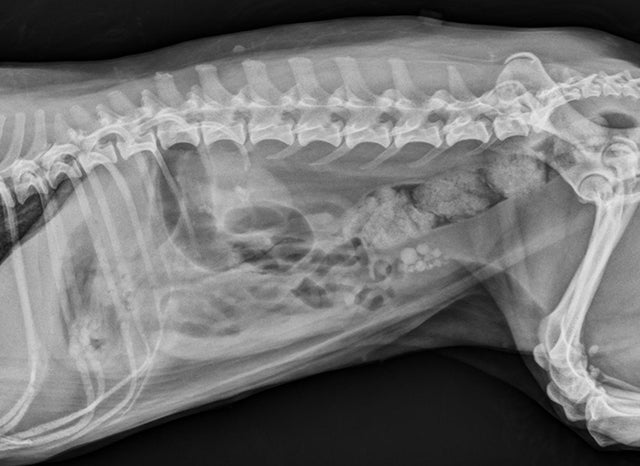

In this complimentary VETgirlBlue Buffalo webinar, Dr. Martha Cline, DACVN reviews the basic principles of preventing bladder stones in dogs and cats – from decreasing urine concentration and precursors to altering urine pH! Tune in for better patient outcomes!